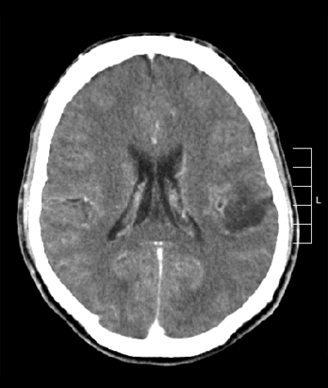

The patient is a 58-year-old woman who was diagnosed at an outside hospital with a World Health Organization (WHO) grade III non–contrast-enhancing right frontal anaplastic astrocytoma, with spread into the genu of the corpus callosum.